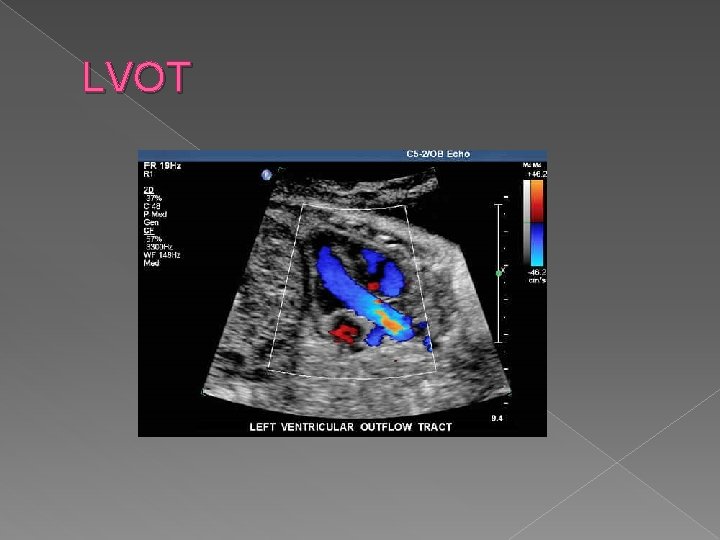

LVOT � Left ventricular outflow tract view (LVOT) › ID origin of aorta from the left ventricle › Sagittal section shows aortic arch and its branches

LVOT

LVOT